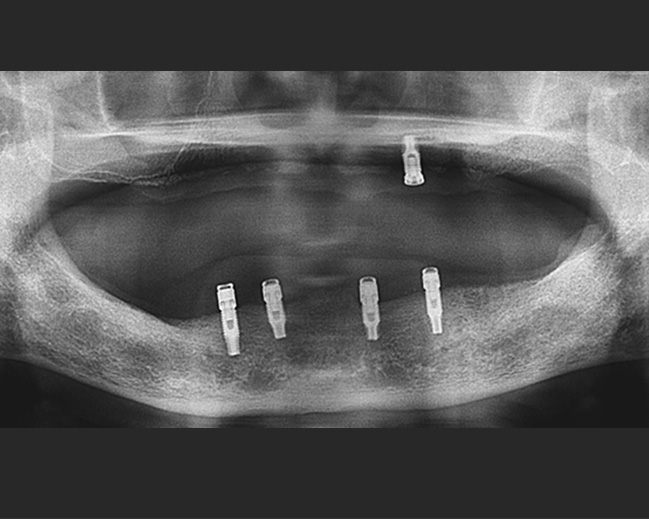

implant 임플란트

실패할 임프란트는 심지 않겠습니다.

미소드림의 임플란트 환자는 95% 소개 환자입니다.